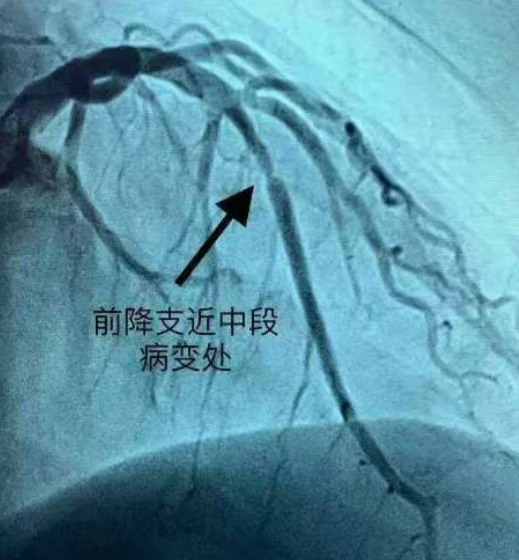

于是就谨遵医嘱也开始用药吃上他汀了,但随着生活管理以及日常用药,低密度脂蛋白都降到1.4以内了,再降就是营养不良了,复查却发现前降支还是堵了,于是就不明所以了,感觉老天爷不公平,为啥自己做得很好还是这样了?这不是管了个寂寞吗?所以今天跟大家讲讲这方面问题

所以想要维持好自身情况,避免心脑血管疾病,我们要从全方面综合管理,而不是只盯着血脂降没降,认为它降下去了就等于万事大吉,这是不能够直接画等号的,大家明白了吗?你前降支现在还好吗?